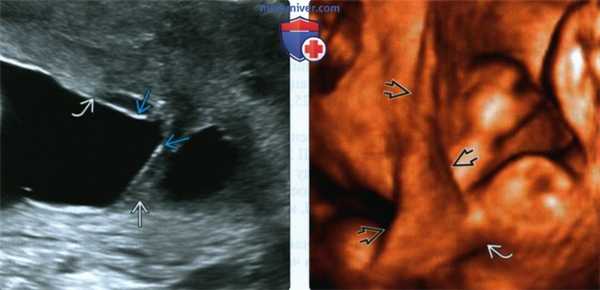

(Слева) ТАУЗИ. Определяется фиброзный тяж, полностью пересекающий полость матки. Амнион обернут вокруг синехии, которая лежит отдельно от края плаценты. Следует дифференцировать данное состояние от плаценты, окруженной валиком, при которой тяж соединяет противоположные края плаценты.

(Справа) 3D УЗИ. Определяется листовидная синехия треугольной формы. Верхняя конечность не фиксирована и свободно перемещалась при исследовании в режиме реального времени.

2. УЗИ при внутриматочных синехиях у беременной:

• Тяжистая структура, пересекающая полость матки:

о Толщина варьирует

о Свободный край булавовидный или отсутствует

о Гипоэхогенная центральная часть (рубец) лежит между более гиперэхогенными слоями (оболочки)

о Y-образная выемка в месте прикрепления

• Плацента может граничить с синехией или, что встречается чаще, оборачивать ее

• Плод свободно перемещается вокруг амниотической перегородки

• При ЦДК может определяться кровоток

о Для уточнения морфологии выполняют 3D УЗИ:

- Может иметь вид треугольной складки